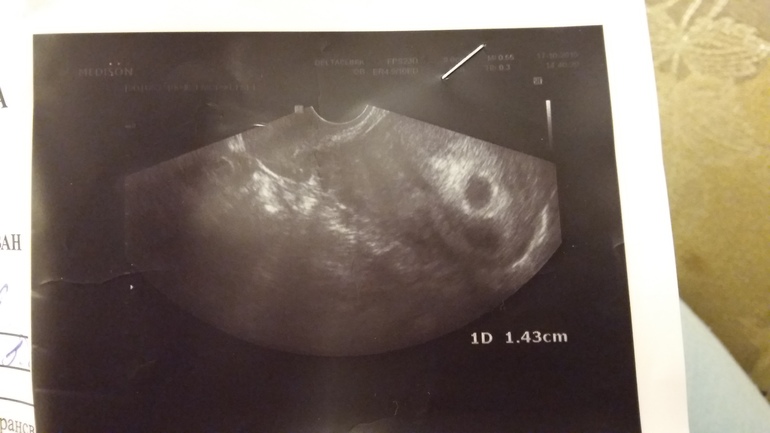

Доброе время суток! В выходные делала узи (3,5 недель по узи) ,гиня сказала отслойка плаценты,но выделений нет.снимок увидела дома, смутило одно, прчему два "кружка"? Или это двойня? На прием только 2.11.,а голова только этим и забита!

Я в инете похожие фото видела,очень похоже на двойню.но гиня несказала про двойню.сравниваю по старым своим узи,тк и с первой была отслойка,но таких пропорциональных кругов нет. Как считаете,на каком сроке точно скажут?

У меня так же , как у вас) в дневнике посмотрите. Гинеколог сказала, что это желчный мешочек)

Чёткий кружок - плодное яйцо. Ниже менее чёткий и есть гематома, которая и сделала вам отслойку.

Гематомы бывают разные. Это я как врач вам говорю. И ваш узист именно это имела в виду.

Мария Ч

Естественно это предположение и возможно это полость матки, которая спадётся. Что бывает крайне редко. Не всегда при гематомах бывают выделения - если она в центре, она может рассосаться в последующем или инкапсулироваться и выйти уже только с родами. Может начать выходить позже. Вариантов много.